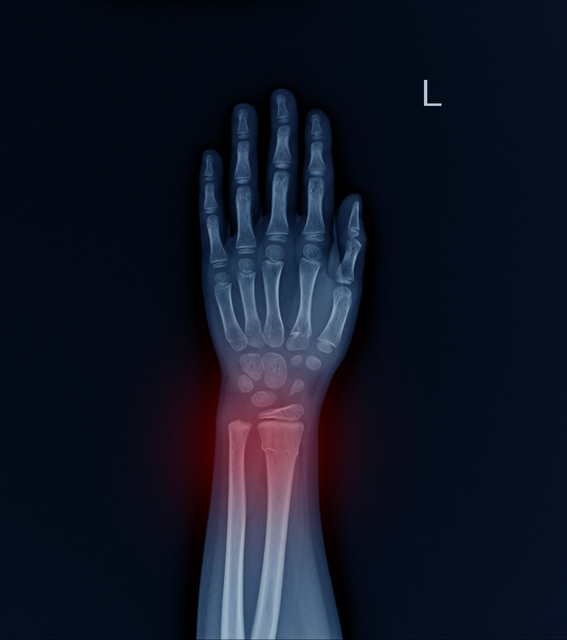

여러분은 자신의 뼈가 얼마나 건강한지 아시나요? 우리 몸을 지탱하는 뼈, 평소에는 그 존재를 잊고 살지만 문제가 생기면 삶의 질을 크게 떨어뜨릴 수 있습니다. 그 중에서도 '골다공증'은 특히 주의해야 할 질환입니다. 골다공증은 '침묵의 질환'입니다. 서서히, 그리고 조용히 우리의 뼈를 약하게 만듭니다. 대부분의 사람들은 심각한 골절이 일어나기 전까지 자신에게 골다공증이 있다는 사실을 모르고 지냅니다. 하지만 그때는 이미 늦었을 수 있습니다. 오늘은 골다공증의 위험성에 대해 자세히 알아보려 합니다. 특히 저에너지 골절이라는 개념을 통해, 왜 골다공증을 방치해서는 안 되는지 이해해 보겠습니다.1. 골다공증의 실태 골다공증은 생각보다 훨씬 흔한 질환입니다. 국제골다공증재단(IOF)에 따르면, 전 세계적으로 5..